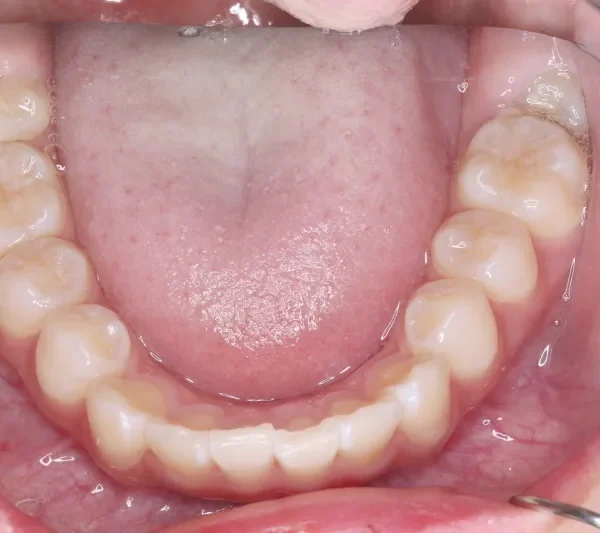

下の歯がずれて生えています。

こどもの歯は下の2本しか抜けていませんが、放っておくとガタガタがきつくなるので、早い段階からの治療としました。

初診